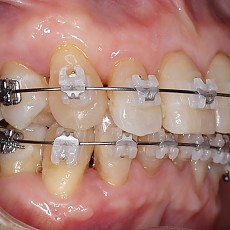

시술전후사진 6 페이지

Total 189건 6 페이지